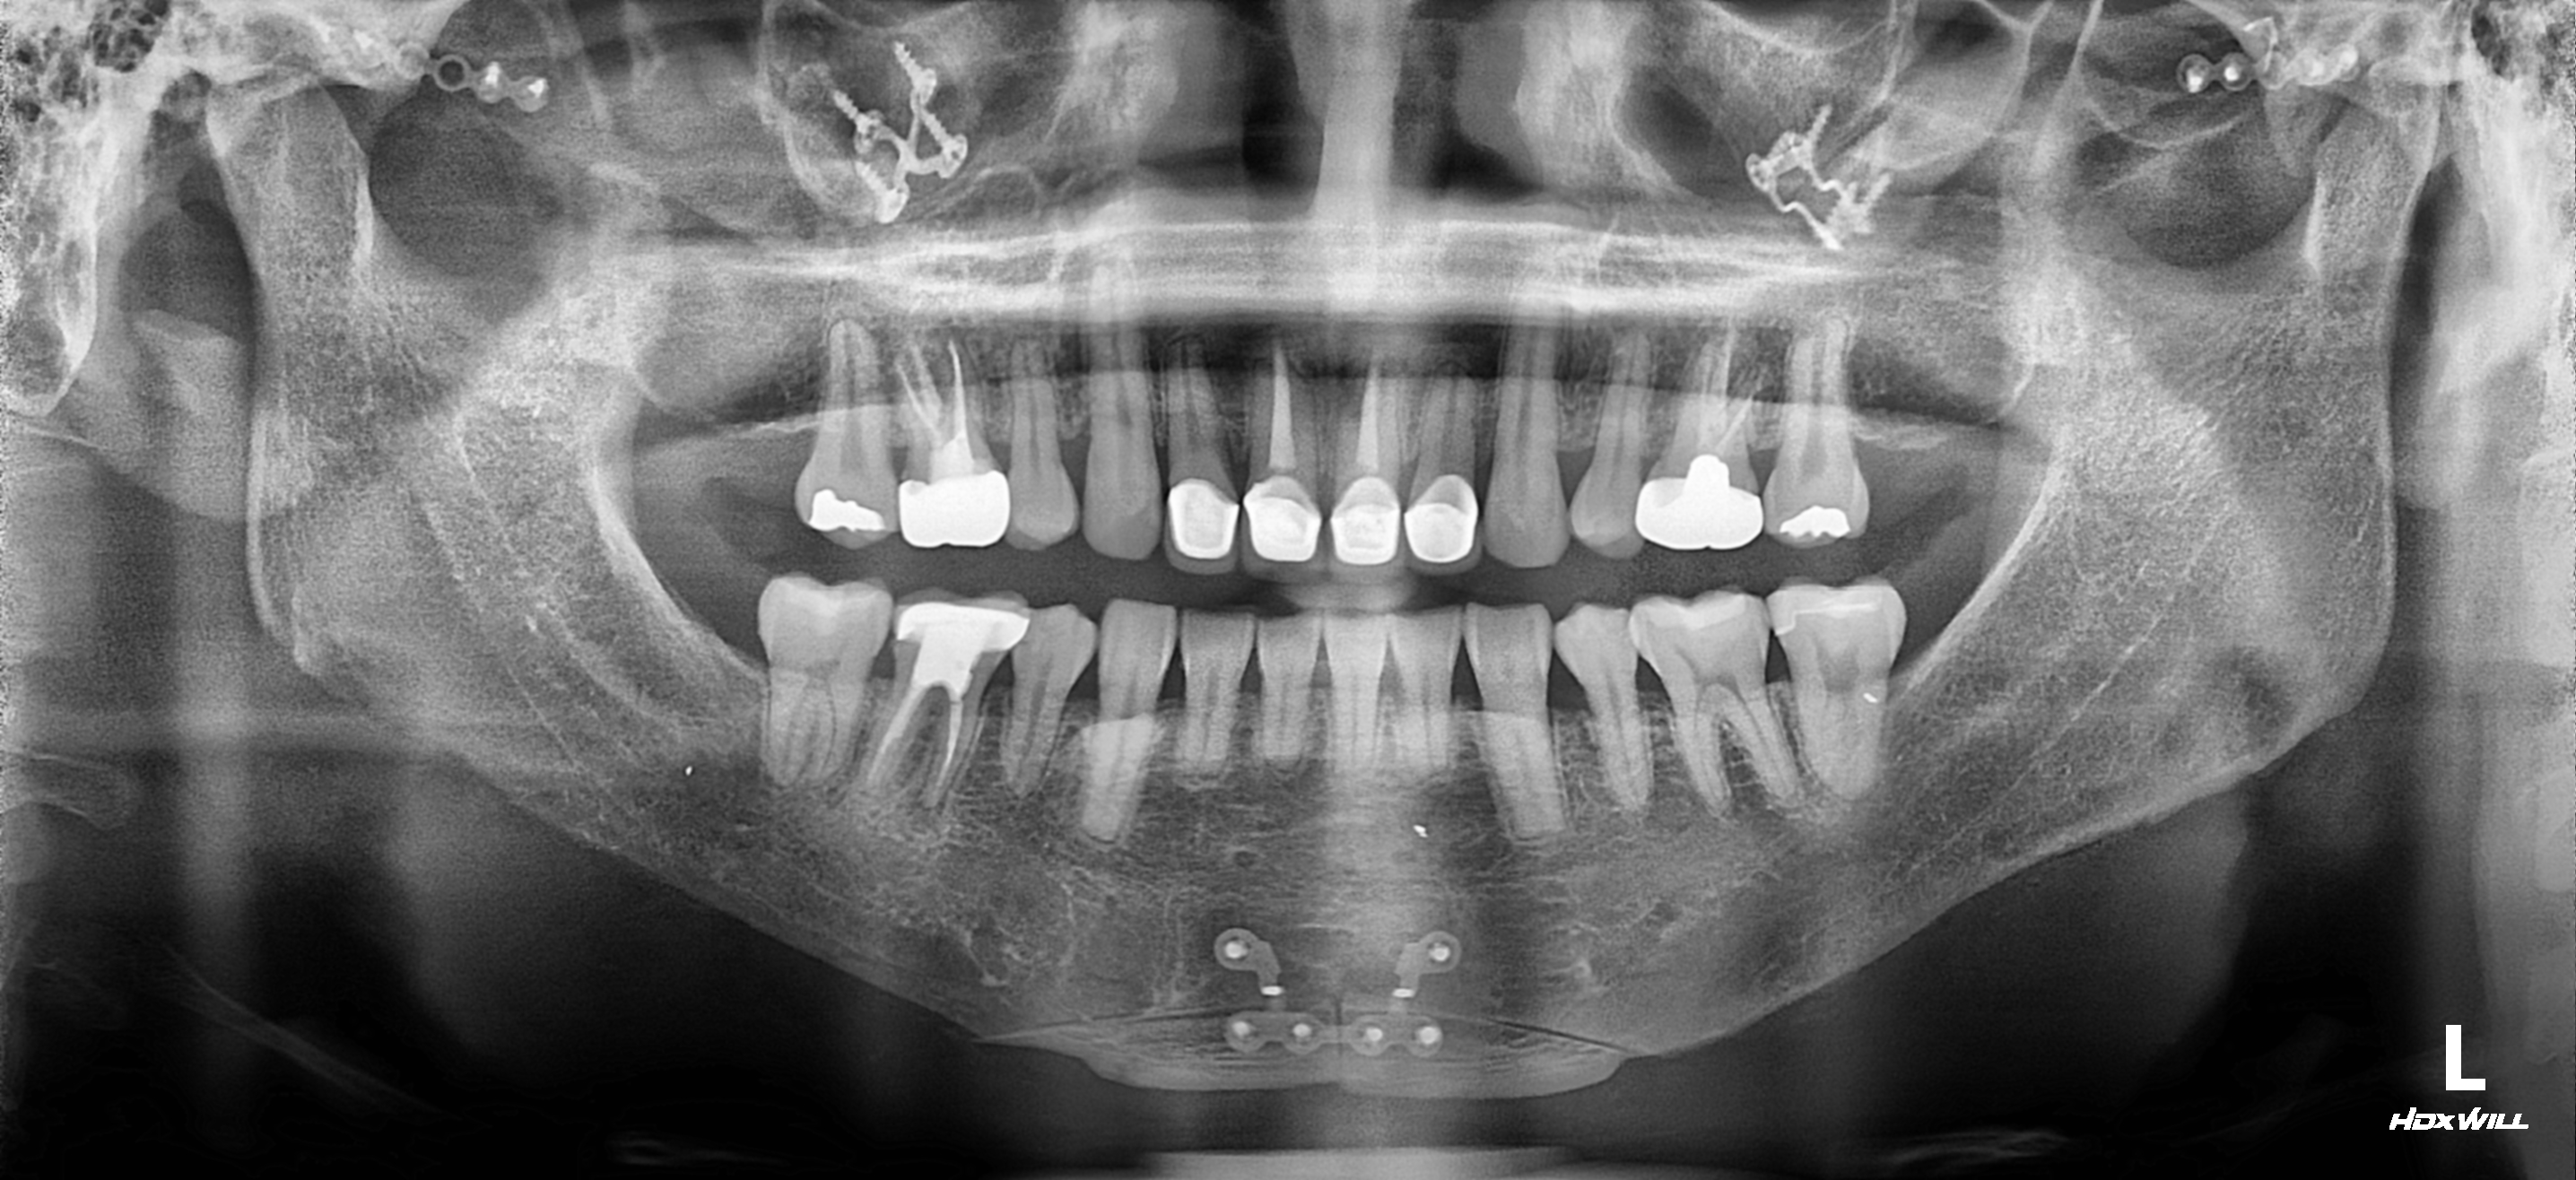

1. 원장님 말씀대로 턱끝을 다시 후방으로 이동시켜야될 목표를 가지고 수술을 계획을 세워야될거 같습니다

3. 일단 원장님이 말씀하신대로나온 주걱턱 느낌 턱끝을 뒤로 후퇴 시킬려고생각합니다 후퇴 시키는 방법ㅇ 중에 두가지를 고려하고 있습니다 일단첫번째 방법으론 기존 절골선을 이용하여 다시 절골후 후퇴 시키는 방법 아래 도완 첨부합니다 삼각형식으로 파서 절골해서 올려 부치는 방법 장단점좀 알려주세요